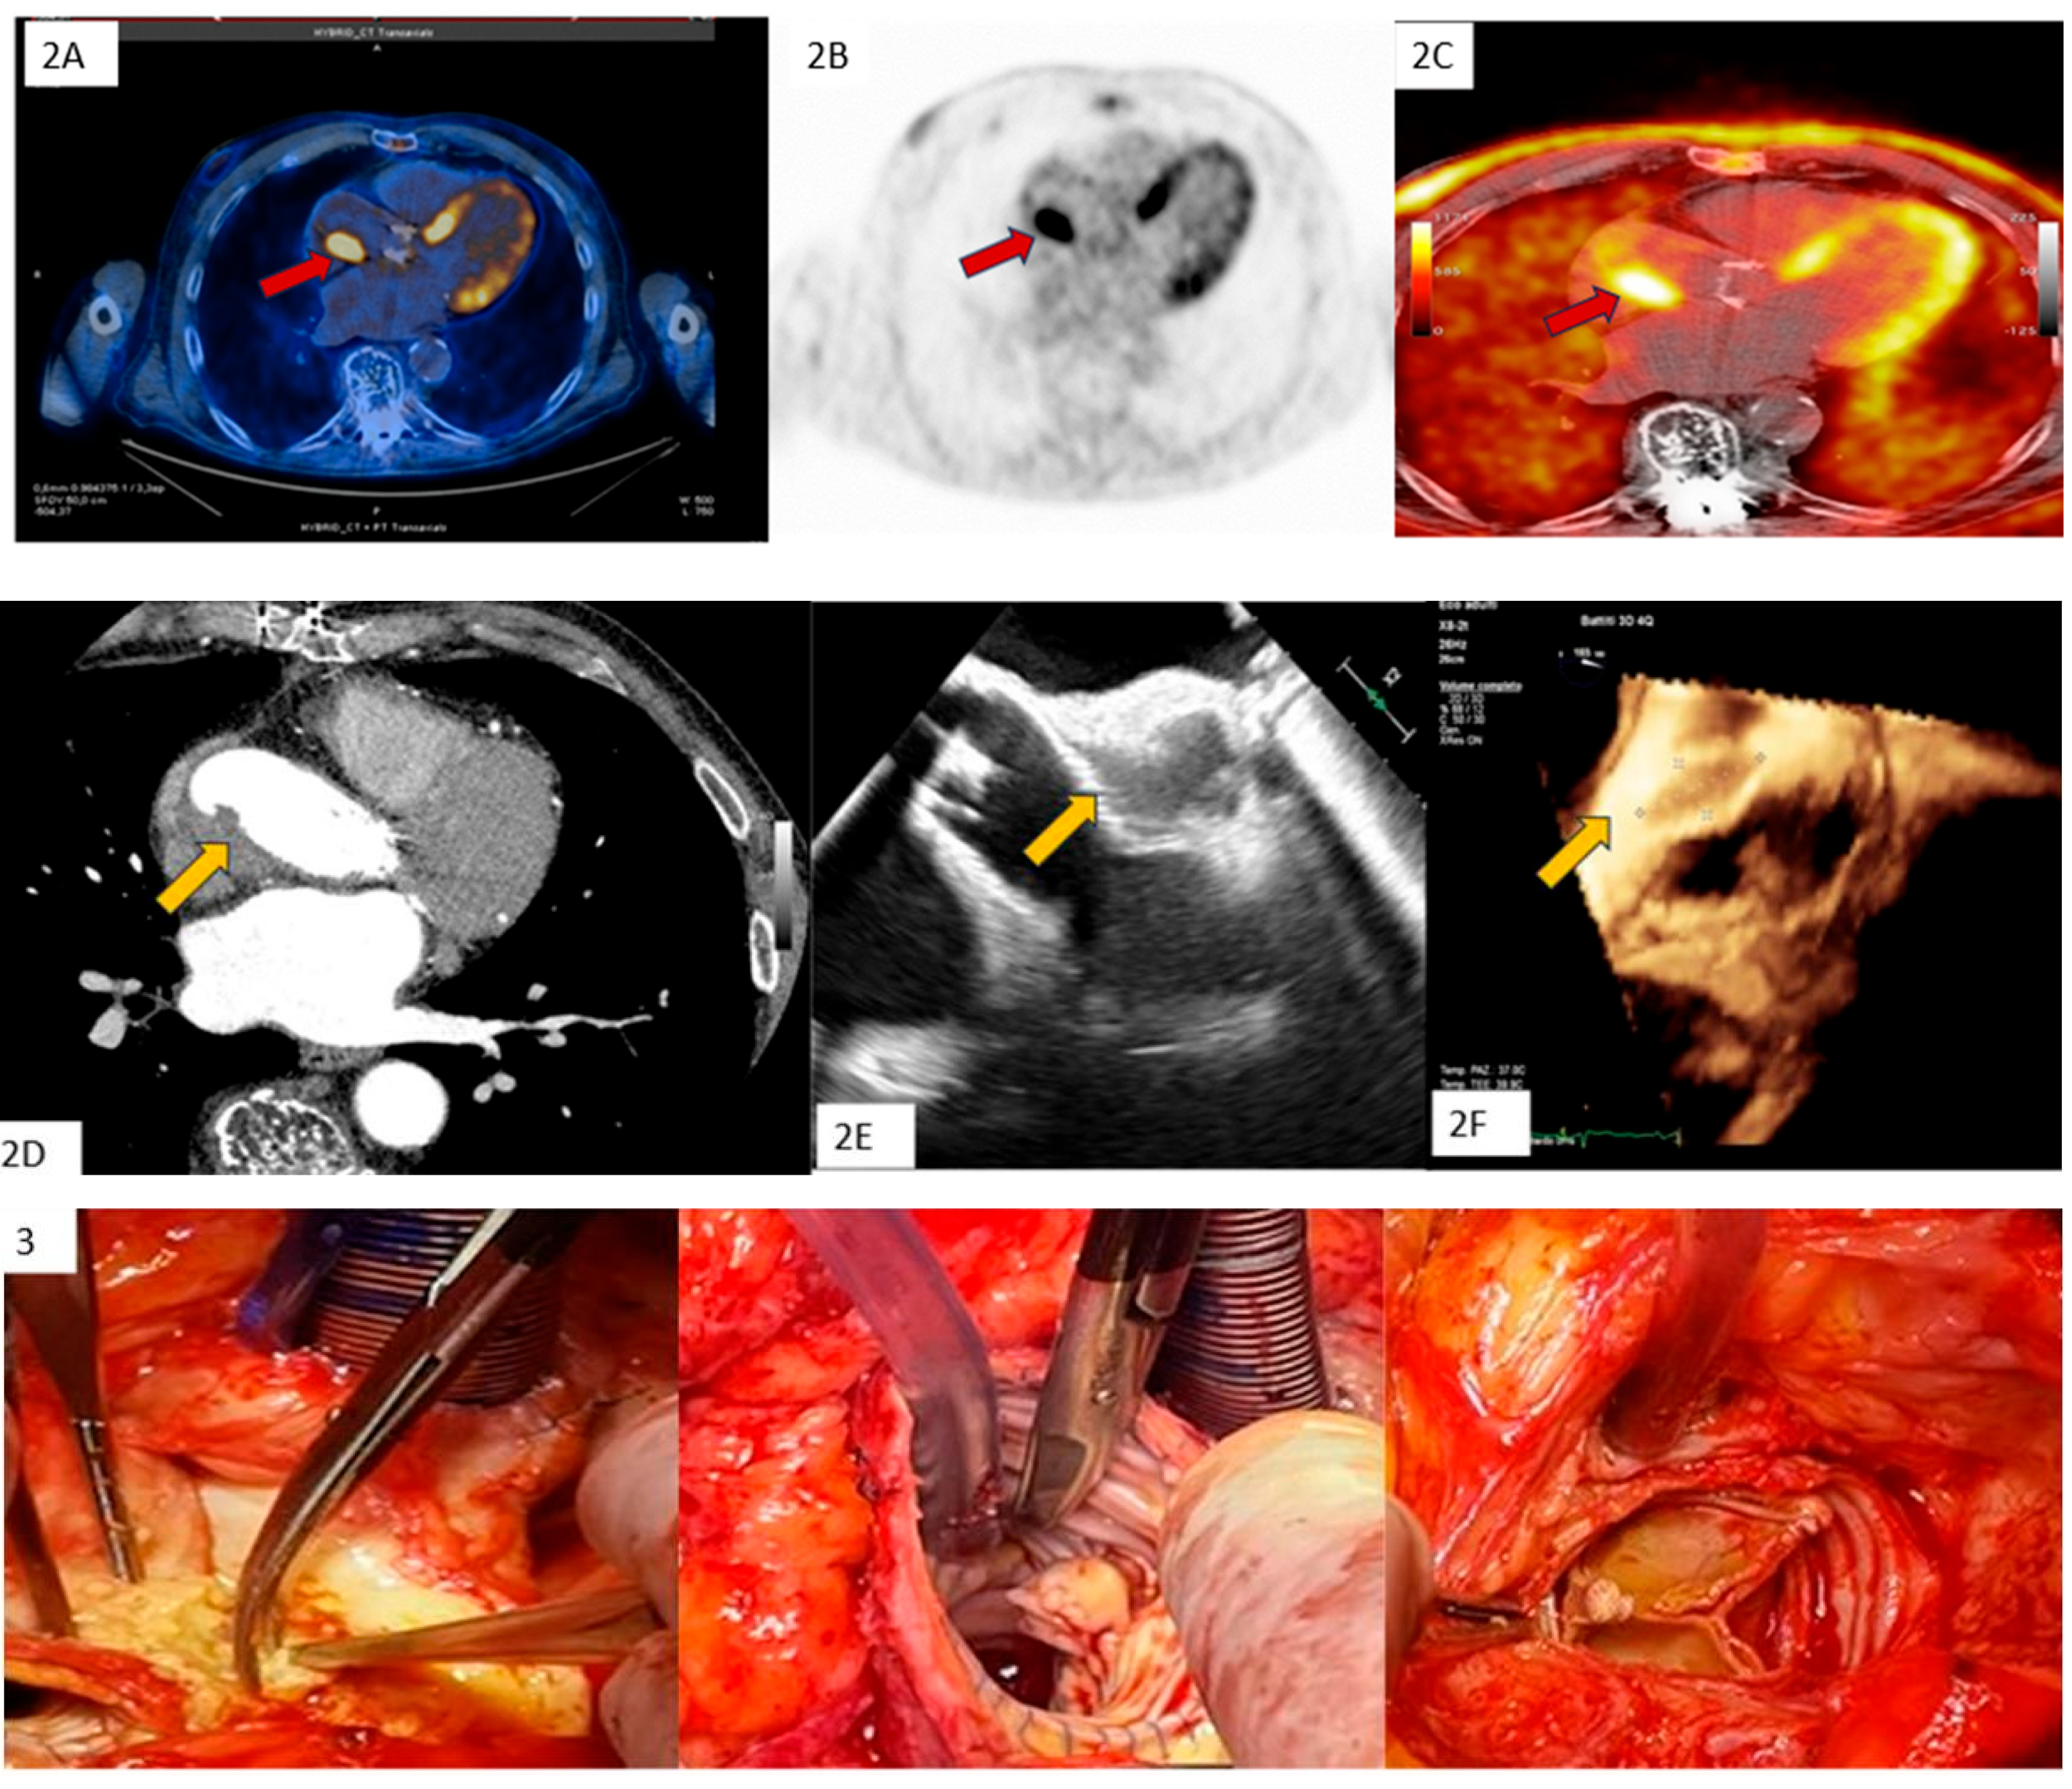

| Clinical Case 3. Unexpected IE in at-risk patient. Female, 80 years old, who underwent previous breast cancer treatment (surgery, chemotherapy, radio therapy). Due to symptomatic severe mitral regurgitation, the patient underwent surgical mitral valve replacement with a biological prosthesis. A 3-month follow-up transthoracic echocardiogram (TTE) showed a normally functioning bioprosthesis. Six months after surgery, the patient was hospitalized for pulmonary edema coincident with high-ventricular rate atrial fibrillation responsive to medical treatment. During the subsequent month, the patient showed transient low-grade fever with a mild increase in PCR and leucocytes together with X-ray evidence of pulmonary infiltrate suggesting pneumonia. Thus, empirical antibiotic therapy was started in addition to cardiac medications (beta-blocking agent, angiotensin II inhibitor, edoxaban). A subsequent 3-day TTE (picture A) showed an unexpected iso-echogenic mass on the atrial surface of the mitral bioprosthesis. Due to concomitant anticoagulant therapy, IE was suspected instead of valve thrombosis with admission to our hospital. On admission the patient showed a stable clinical condition without fever or symptoms. Clinical examination showed a normal clinical condition with sinusal rhythm. Despite a low clinical probability of IE, due to echo-imaging, blood culture was carried out showing S. epidermidis. Focused antibiotic therapy, including Tazocin and Daptomicin, was started. Subsequent 6 h fasting Transesophageal Echocardiography (picture A = 2D-TEE; pictures 1–3 = 3D-TEE) showed a large iso-echogenic mass with bifurcated morphology (maximum diameter 25 × 10 mm). The mass was inserted on the atrial surface of the posterior prosthetic leaflet with annular infiltration and diastolic prolapse in the valvular ostium. Due to the high risk of embolism, the patient underwent a total body CT scan to exclude systemic embolization and subsequent emergency surgery. Surgical inspection (4, yellow arrow) and histological examination together with S. epidermidis isolation confirmed IE diagnosis. The clinical course was uneventful. This clinical case underscores the importance of clinical alert for unexpected at-risk IE requiring emergency surgery, despite a subtle and atypical clinical presentation.  |